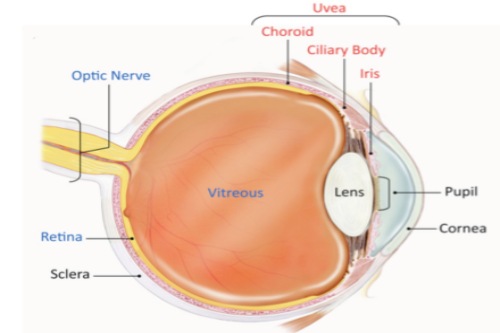

糖尿病视网膜病变,也被称为糖尿病性视网膜病变或糖网病。它是由于糖尿病导致视网膜微血管受损,进而影响视力。